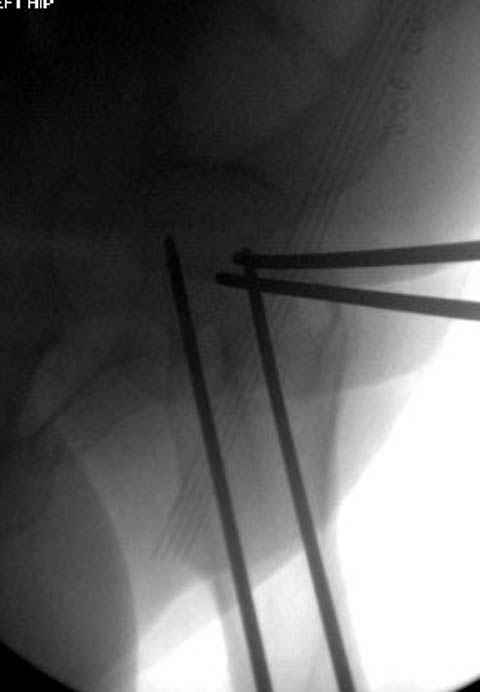

Долгое ожидание повышает риск АВН головки,

рекомендуется ургентная фиксация шейки в первые сутки, а в дальнейшем таз.

В данный момент скелетное вытяжение поучается через перелом шейки, а фиксированный перелом шейки будет участвовать в процессе вытяжения через каннюлированные шурупы.

Перелом шейки смогли зафиксировать через пару дней, ацетабулум до сих пор не оперирован, на вытяжении.